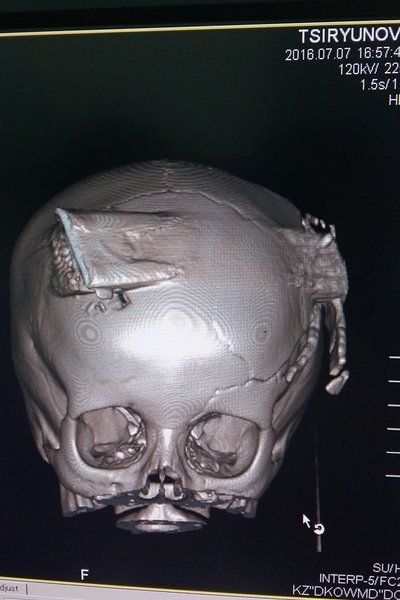

Когда ребенка, находившегося в коме, привезли в Днепр и сделали томограмму, оказалось, ситуация еще серьезнее, чем предполагали врачи. Даня, по сути, получил осколочное ранение с повреждением тканей головного мозга. Острым ножом ребенку отсекло часть левого полушария, которая отвечает за правую половину тела и речь. Опыта проведения подобных операций у детских нейрохирургов не было. Такие травмы в Днепре могут оперировать только врачи областной больницы имени Мечникова, которая за последние два года превратилась в главный прифронтовой госпиталь. Когда с просьбой о помощи из детской больницы позвонили заведующему нейрохирургией областной клиники профессору Андрею Сирко, тот сразу порекомендовал своего коллегу – нейрохирурга высшей категории Александра Марченко.

«Операция началась около семи часов вечера, – рассказывает Александр Марченко. – Извлекать нож сразу было опасно: открылось бы кровотечение, которое трудно остановить. Кусок металла вошел в левый висок, прорезал насквозь черепную коробку и вышел справа, причинив внутри серьезные повреждения. Нож зажал перебитые сосуды, и добираться до него нужно было очень осторожно, ведь для маленького ребенка потеря даже литра крови смертельно опасна. Сначала мы провели трепанацию черепа, удалив большой участок кости на макушке, потом постепенно начали убирать поврежденные части мозга. Когда вскрыли черепную коробку, почувствовали гнилостный запах: вместе с грязной железкой в рану попали земля, трава. Кроме кровотечения, ребенку грозили отек мозга, энцефалит, заражение крови. Однако за время войны мы разработали свою методику, позволяющую избежать этих осложнений: кусочек собственной ткани человека пропитывается антибиотиком и помещается в рану, создавая неблагоприятную для развития инфекции среду. Этот метод и применили».

Когда более чем четырехчасовая операция близилась к концу, Владимир Агафонов осторожно вытащил пинцетом металлическую пластину. Даня за время операции потерял еще около 700 граммов крови. Операция закончилась успешно.